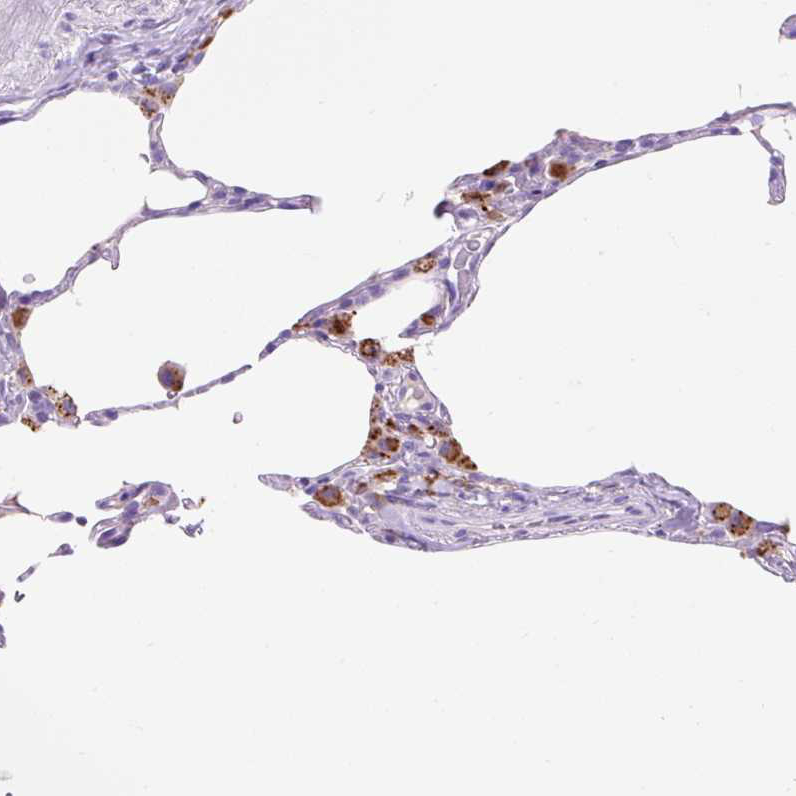

Immunohistochemical staining of human cerebral cortex, lung, prostate and testis using Anti-HEXB antibody HPA055409 (A) shows similar protein distribution across tissues to independent antibody HPA056010 (B).